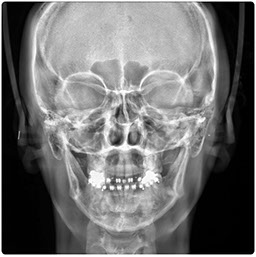

Eagle 2D Pan/Tele

El Eagle 2D Pan/Tele ofrece todos los exámenes en el perfil panorámico (panorámica estándar, senos maxilares, baja dosis, bitewing, ATM, ortogonalidad perfeccionada, panorámica infantil y bitewing ortogonalidad perfeccionada) y todos los exámenes en el perfil cefalométrico (Posteroanterior, Antero-posterior, 45 Grados, Lateral, Carpal, PA de Walters, Axial Bazal, Hirtz).

Telerradiografía Antero Posterior